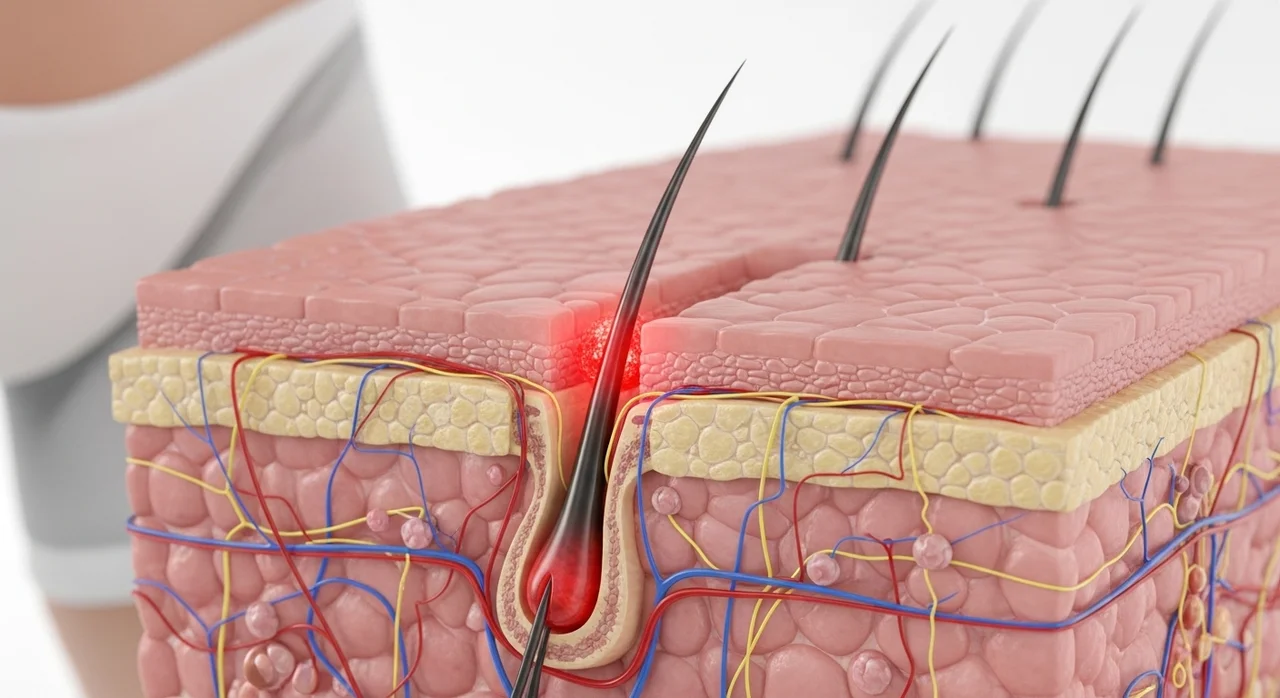

수술적 치료: 최소절개와 흉터 최소화

수술 방법은 뼈를 일부 절제하고 각도를 맞추는 절골술이나, 부족한 피부를 연장하는 피부 이식술 등이 시행됩니다. 최근에는 최소 절개 기법을 사용하여 흉터를 최소화하고 회복 기간을 단축시키는 방향으로 진행됩니다. 수술 후에는 약 4~6주 정도의 고정 기간과 재활 치료가 필요합니다.